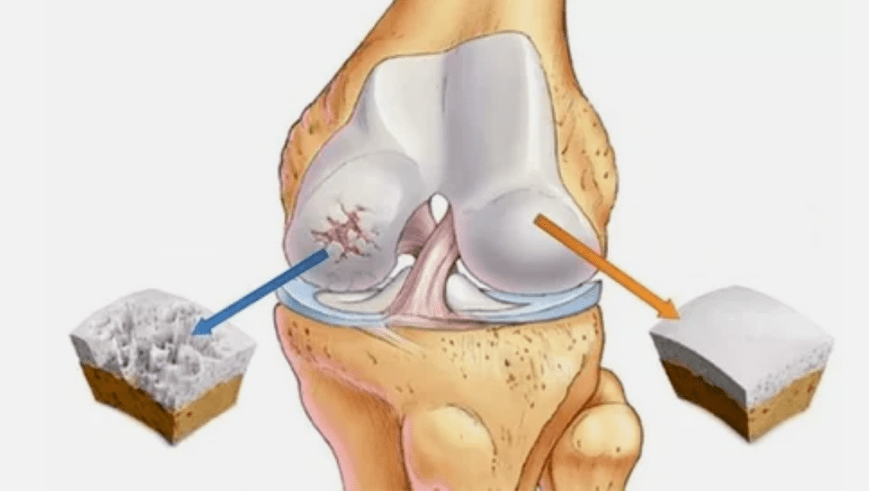

- A lesão primária afeta a cartilagem hialina. Em caso de distúrbios circulatórios, ocorre deterioração patológica do poder. É a primeira etapa ou causa, que pode ocorrer artrose.

- Patologias de revestimento de hialina. O afinamento da cartilagem leva à substituição de seus tecidos patológicos - estruturas ósseas.

- Os crescimentos anômalos aparecem na cartilagem - osteófitos.

- A violação surgida da anatomia natural da cartilagem e dos ossos provoca a sobrecarga de áreas saudáveis da cartilagem. A destruição de tecidos articulares sem tratamento está progredindo constantemente e leva à incapacidade.

Quando o grau de doença aumenta, os processos patológicos ainda são agravados. No final, toda a cartilagem de Hyalin é destruída.